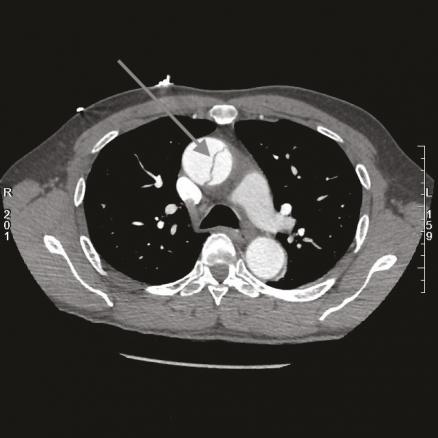

Cet homme de 55 ans, sans antécédent, avait appelé le 15 pour une douleur thoracique irradiant dans la mâchoire et des paresthésies du bras droit, après un effort de marche. À l’examen la pression artérielle était de 165/85 mmHg symétrique, les pouls étaient symétriques, et il n’y avait pas de déficit moteur des 4 membres. L’électrocardiogramme montrait un léger sous-décalage du segment ST en DIII et AvF. Le médecin du SMUR retenait le diagnostic de syndrome coronaire aigu « non ST+ » et orientait le patient vers une unité de soins intensifs cardiologiques où la tomodensitométrie thoracique (fig. 1) révélait finalement une dissection aortique de type A étendue de la racine de l’aorte jusqu’à l’ostium de l’artère carotide primitive gauche (fig. 2).